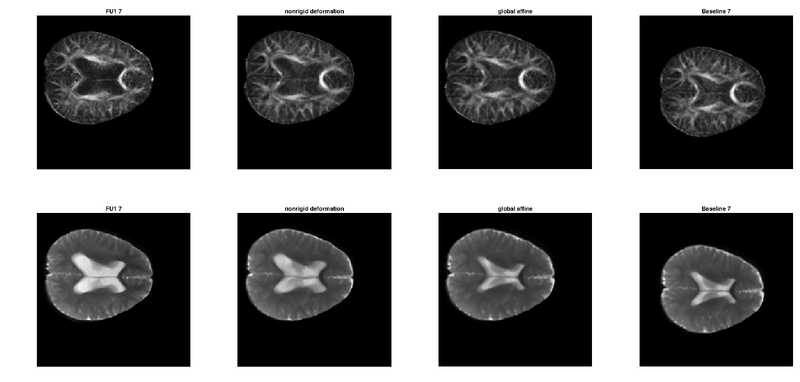

Revision as of 23:21, 6 January 2017 by Henrikgjensen (talk | contribs) (Nonrigid registration of child cancer DWI. Intra-subject (FllowUp to Baseline), poor quality and resolution (around [0.86, 0.86, 6.5] mm). Top: FA, Bottom: b0 image. From the left: (1) interpolated source, (2) nonrigid registration (compare with source...)

Nonrigid registration of child cancer DWI. Intra-subject (FllowUp to Baseline), poor quality and resolution (around [0.86, 0.86, 6.5] mm). Top: FA, Bottom: b0 image. From the left: (1) interpolated source, (2) nonrigid registration (compare with source), (3) affine registration. (4) interpolated target.

current23:21, 6 January 2017Thumbnail for version as of 23:21, 6 January 20171,496 × 714 (176 KB)Henrikgjensen (talk | contribs)Nonrigid registration of child cancer DWI. Intra-subject (FllowUp to Baseline), poor quality and resolution (around [0.86, 0.86, 6.5] mm). Top: FA, Bottom: b0 image. From the left: (1) interpolated source, (2) nonrigid registration (compare with source...